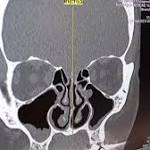

Woman's runny nose was actually fluid from inside her brain

3. A Woman's Runny Nose Turned Out To Be A Cerebrospinal Fluid Leak  BuzzFeed News